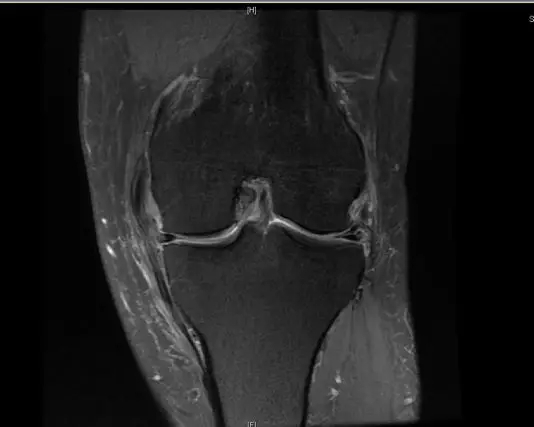

后交叉韧带断裂

从此片可以看出后交叉韧带连续性中断,松弛,增粗,下止点信号增高比较明显,从这个角度看后交叉韧带上止点信号较为正常,但下止点信号明显增高,缺乏韧带止点应有的形态,从这个层面看下止点信号增高,从这个层面看韧带是增粗的,整体信号增高,质地不均一,并且松弛,从这个层面可以看到它的下止点信号增高,缺乏正常的韧带形态特点,所以考虑后交叉韧带断裂。